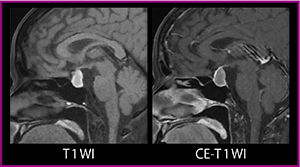

鞍上槽に認められる囊胞様構造は,ラトケ囊胞であることが比較的多い(図3)。T1強調画像で高信号を示すことが多いが,内溶液のムチン濃度によっては低信号となるケースもある。造影T1強調画像では,被膜が濃染され充実部分は見られない。

小児では,頭蓋咽頭腫の症例で鞍上槽の囊胞が認められることが多い。充実部分がない囊胞としては,クモ膜下囊胞の可能性もあるが,造影検査で部分的に濃染され,小児例であることを踏まえると頭蓋咽頭腫と考えていいだろう。なお,頭蓋咽頭腫はX線検査で石灰化が認められる特徴がある。

図3 ラトケ囊胞